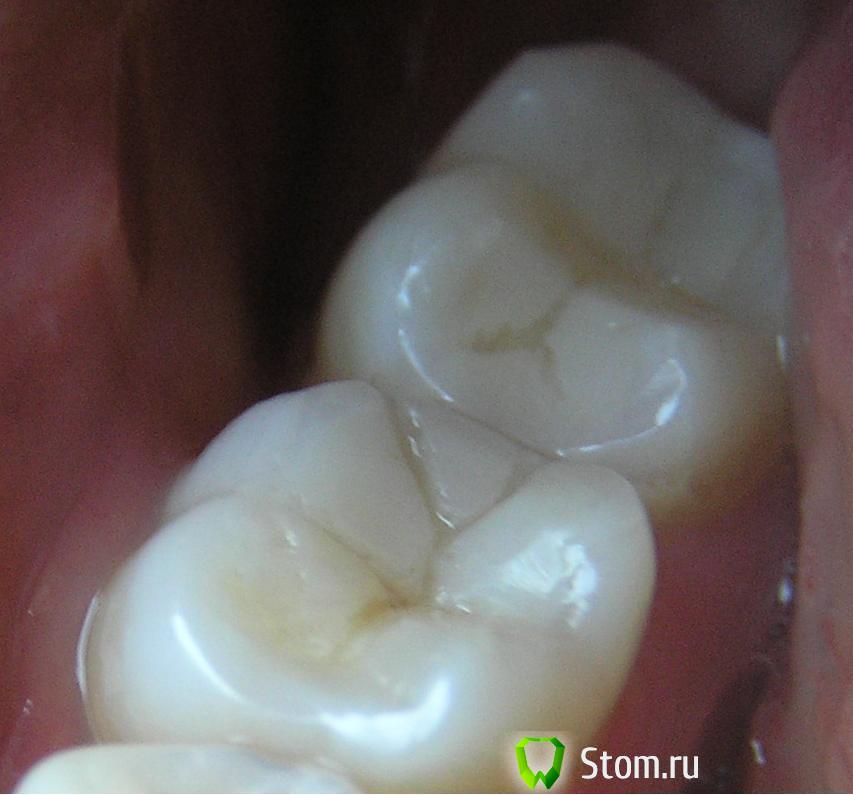

Stella Опубликовано 13 февраля, 2012 Поделиться Опубликовано 13 февраля, 2012 Здравствуйте, 2 недели назад мне на 6,7 зуб поставили другие пломбы- обновили на новые. Сначала было все нормально, но где-то неделю назад заметила трещины (до этого не всматривалась, изначально их точно не было). Что это? Дефект пломбы? Это нужно менять? Также не могу жевать твердую пищу на этой стороне.Спасибо. Ссылка на комментарий

ger_berra Опубликовано 13 февраля, 2012 Поделиться Опубликовано 13 февраля, 2012 Вполне возможно ,что это у Вас не трещины,а пигментация пломбы.Невозможно хорошо отполировать созданные таким образом бороздки между буграми.На неполированную пломбу "цепляется" краситель и кажется,что появилась трещина.Но если пломба или её часть подвижна,то это может быть и трещина.Скажите,пожалуйста,боль появляется ,когда Вы сжимаете или разжимаете зубы? Ссылка на комментарий

Stella Опубликовано 13 февраля, 2012 Автор Поделиться Опубликовано 13 февраля, 2012 Чувствуется, будто это трещина - ноготь проваливается туда. Зубной боли у меня обычно не бывает ни у каких зубов - даже зубы без анестезии лечу. Не знаю, как точно назвать эти ощущения, какой-то дискомфорт, когда жую твердую пищу, поэтому сейчас практически все жую на другой стороне- там все нормально. Ссылка на комментарий

ger_berra Опубликовано 13 февраля, 2012 Поделиться Опубликовано 13 февраля, 2012 (изменено) Чувствуется, будто это трещина - ноготь проваливается туда. Зубной боли у меня обычно не бывает ни у каких зубов - даже зубы без анестезии лечу. Не знаю, как точно назвать эти ощущения, какой-то дискомфорт, когда жую твердую пищу, поэтому сейчас практически все жую на другой стороне- там все нормально.Я Вам рассказала,что вижу по фото.Обратитесь к доктору,который делал эти пломбы.Пусть проверит на предмет преждевременных контактов,т.е. завышение прикуса.Такое тоже бывает.Между зубами зубная нить со щелчком заходит?При выведении не рвётся,не разволокняется? Изменено 13 февраля, 2012 пользователем ger_berra Ссылка на комментарий